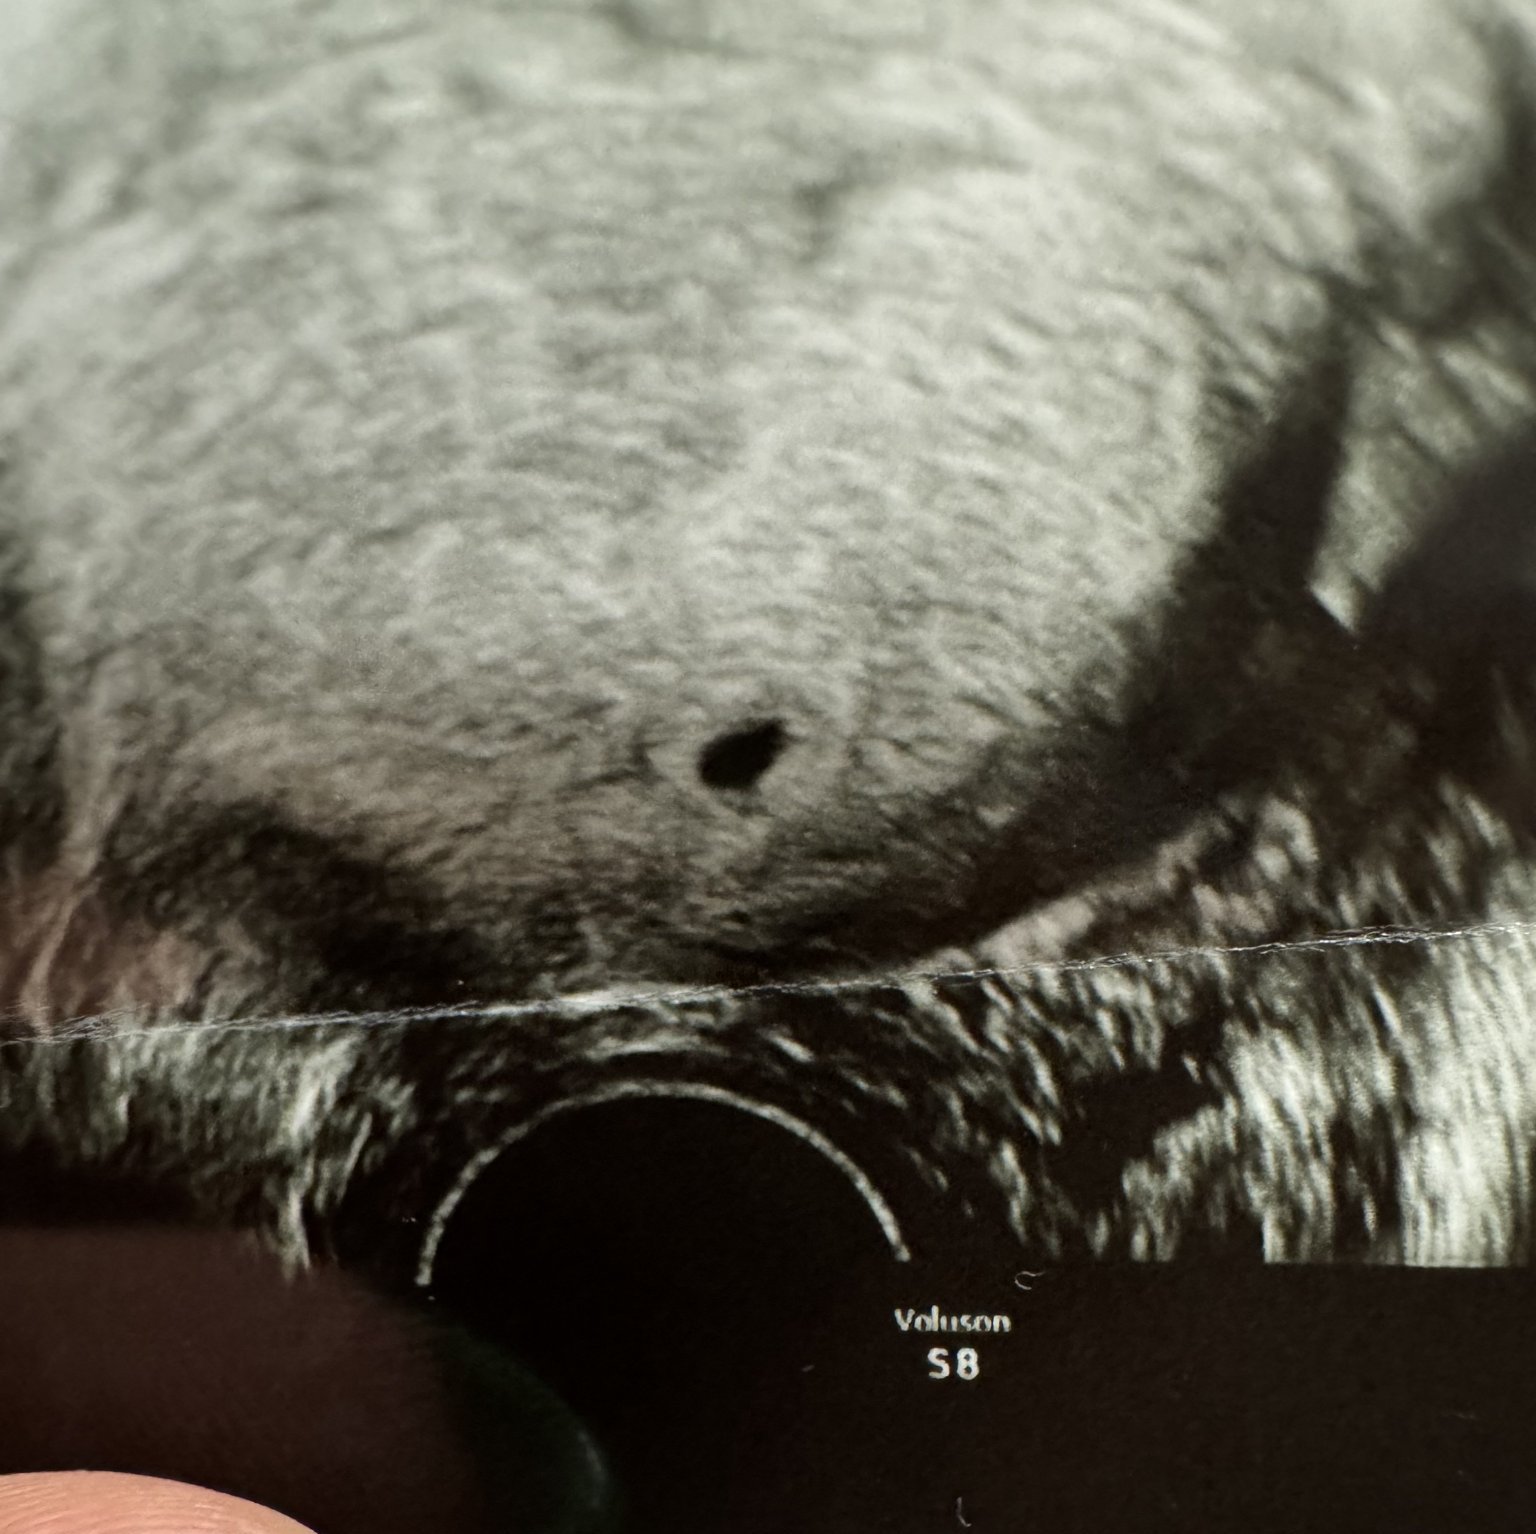

Здравейте момичета, днес бях на преглед и докторът ми видя на видеозона образувание като плод, веднага ми даде тест за бременност, но беше отрицателен. МЦ ми закъснява с 5 дни, прати ме утре на кръвен тест, но просто се чудя ако не е бременност има ли вариант да се обърка дори и от лекар с киста?

Аз бях след спонтанен аборт и нещо много ме наболяваше ниски долу и отидох на лекар да видим какво става и ми казаха, че съм бременна, а аз обясних всичко, че имам спонтанен аборт преди месец, но не тя беше категорична и аз изпратих изпратих снимката от видеозона на моят доктор в София гинеколог - онколог и той ми каза върни се й кажи на въпросната лекарка да си скъса дипломата, защото това е киста която е 8 см., така че вече нищо не ме изненадва.

След 3 + теста днес лекаря ми каза че това е сакче и е маточна бременност! Може ли и вашето мнение?

3 положителни теста, потвърдена бременност от АГ... Какво повече можем да кажем ние?

Честито!